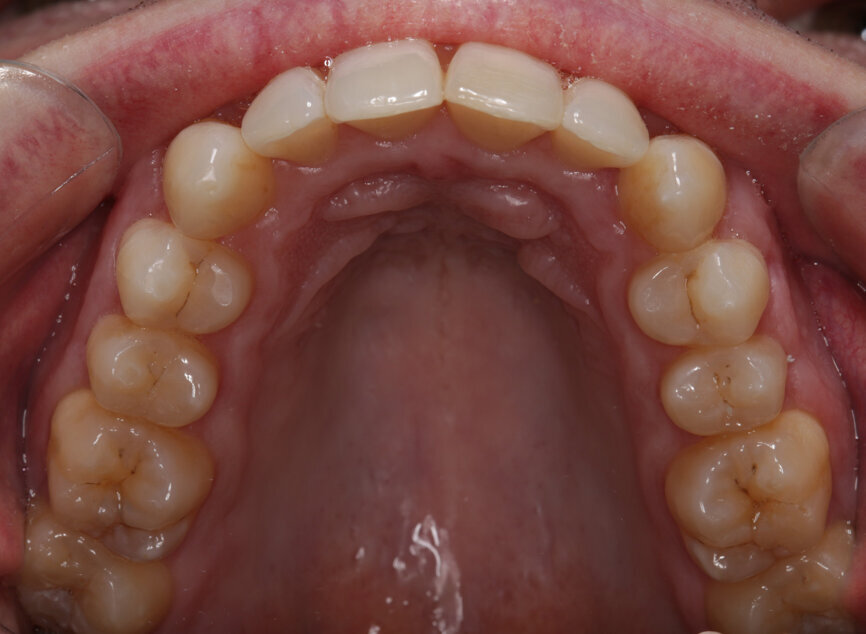

Fig. 5: Pre-treatment upper occlusal view

Two weeks later, the colour and contour of the patient’s gingival margins were as healthy as could be considering the crowding of the teeth. We discussed what treatment with ClearSmile Aligners would involve, such as interproximal reduction (IPR), compliance and risks, and a referral for specialist orthodontics was offered. Preferring to proceed with clear aligners, the patient signed off his full consent, and a two-stage putty impression was taken using a separation wafer. The Archwize digital planning software was used to predict tooth movement and necessary IPR throughout treatment. It suggested that 18 maxillary aligners would be needed.

My examination revealed nothing abnormal with his extra- or intra-oral soft tissue, temporomandibular joint or range of motion. However, his oral hygiene was poor, which was not helped by the crowding of his maxillary anterior segment. In addition, tooth #48 was carious. I carried out a full orthodontic assessment (Table 1) and took photographs.